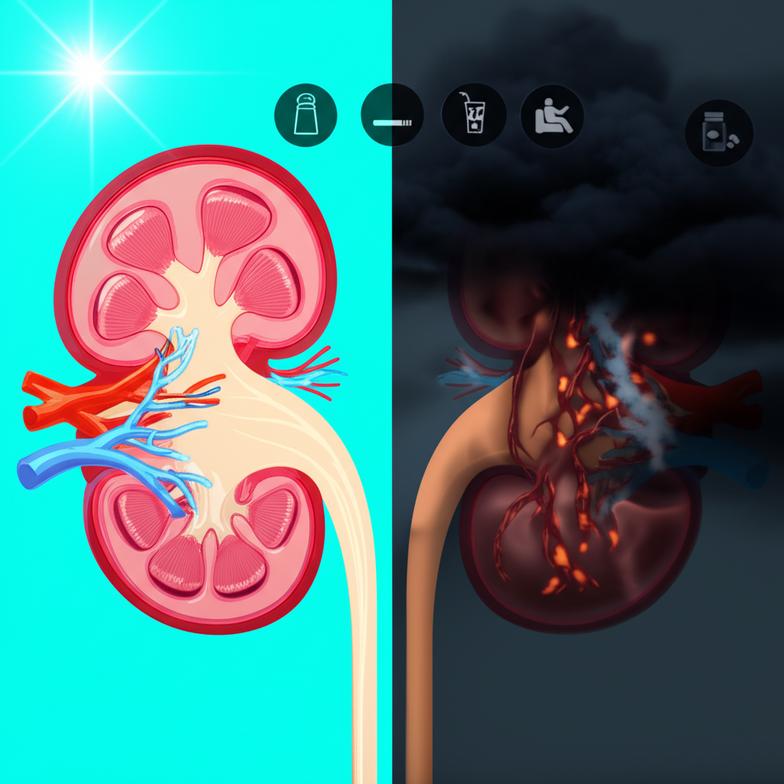

5 พฤติกรรมยอดฮิตที่เร่งไตพัง: แนวทางสู่ kidney failure prevention

พฤติกรรมในชีวิตประจำวันที่เรามองข้ามไปหลายอย่าง กลับเป็นปัจจัยสำคัญที่บั่นทอนสุขภาพไตอย่างช้าๆ ซึ่งหากปรับเปลี่ยนได้ทัน จะเป็นหัวใจหลักของการทำ kidney failure prevention:

- บริโภคอาหารรสจัด โดยเฉพาะเค็มจัด: การได้รับโซเดียมมากเกินไป ทำให้ไตต้องทำงานหนักขึ้นเพื่อขับโซเดียมส่วนเกินออกจากร่างกาย ส่งผลให้เกิดภาวะความดันโลหิตสูง ซึ่งเป็นสาเหตุสำคัญที่ทำลายหลอดเลือดในไตและเร่งการเสื่อมของไต อาหารแปรรูป ขนมขบเคี้ยว และอาหารสำเร็จรูปมักมีโซเดียมสูง

- ดื่มน้ำไม่เพียงพอ: การดื่มน้ำน้อยทำให้เลือดมีความเข้มข้นสูง ไตต้องใช้พลังงานมากขึ้นในการกรองของเสีย นอกจากนี้ยังเพิ่มความเสี่ยงต่อการเกิดนิ่วในไต ซึ่งสามารถนำไปสู่การติดเชื้อและทำลายเนื้อไตได้

- การรับประทานยาแก้ปวดกลุ่ม NSAIDs ติดต่อกันเป็นเวลานานโดยไม่ปรึกษาแพทย์: ยาแก้ปวดลดอักเสบที่ไม่ใช่สเตียรอยด์ (Non-Steroidal Anti-Inflammatory Drugs: NSAIDs) เช่น ไอบูโพรเฟน หรือนาพรอกเซน หากใช้ติดต่อกันเป็นเวลานานหรือในปริมาณสูง สามารถลดการไหลเวียนเลือดไปเลี้ยงไต ทำให้เนื้อไตเสียหายได้

- บริโภคน้ำตาลและคาร์โบไฮเดรตแปรรูปมากเกินไป: การได้รับน้ำตาลและคาร์โบไฮเดรตแปรรูปในปริมาณมากอย่างต่อเนื่อง ไม่เพียงเพิ่มความเสี่ยงต่อโรคเบาหวาน ซึ่งเป็นสาเหตุอันดับหนึ่งของโรคไตวาย แต่ยังส่งผลให้เกิดการอักเสบในร่างกายและหลอดเลือด รวมถึงหลอดเลือดในไต

- นอนหลับไม่เพียงพอและภาวะเครียดเรื้อรัง: การนอนหลับพักผ่อนไม่เพียงพอส่งผลกระทบต่อระบบฮอร์โมนในร่างกาย ทำให้เกิดการอักเสบและเพิ่มความดันโลหิตได้ ซึ่งเป็นปัจจัยเสี่ยงต่อการทำลายไต เช่นเดียวกับความเครียดเรื้อรังที่กระตุ้นการหลั่งฮอร์โมนคอร์ติซอล ทำให้ร่างกายเข้าสู่ภาวะอักเสบต่อเนื่อง